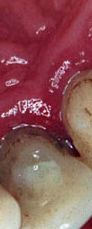

pase el ratón sobre las piezas para ver: bolsa, recesión y movilidad